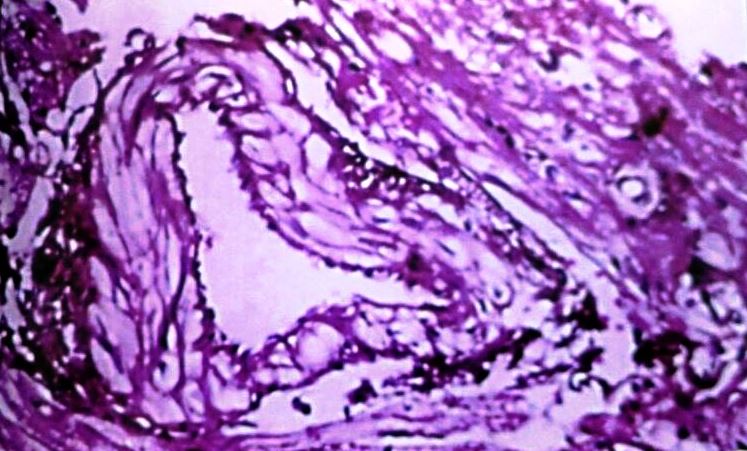

Asending Aorta

Histological study showed that control group had completely normal arteries without any lesion in intima or media. In our study athero fed rabbits showed well developed atheromatous plaque protruding in to the lumen of the aorta. There were many foamy (lipid-laden) macrophages and dense fibrous tissue layer in the plaque could be seen. Media was also showing foam cell. The animals consuming the C. verum along with high cholesterol, the severity of lesions were significantly reduced, three layers of aortic wall were distinct, and only few lipid-laden cells were present in the medial layer when compared with the rabbits consuming the high cholesterol diet (group II) (fig. 3-6).

Fig. 3: Ascending aorta of control rabbit

Fig. 4: Ascending aorta of rabbit after Athero diet feeding for 120 d

Fig. 5: Ascending aorta of rabbit-Athero Diet+C. verum 200 mg concurrent (120 d)

Fig. 6: Ascending aorta of rabbit-Athero Diet+C. verum 300 mg concurrent (120 d)